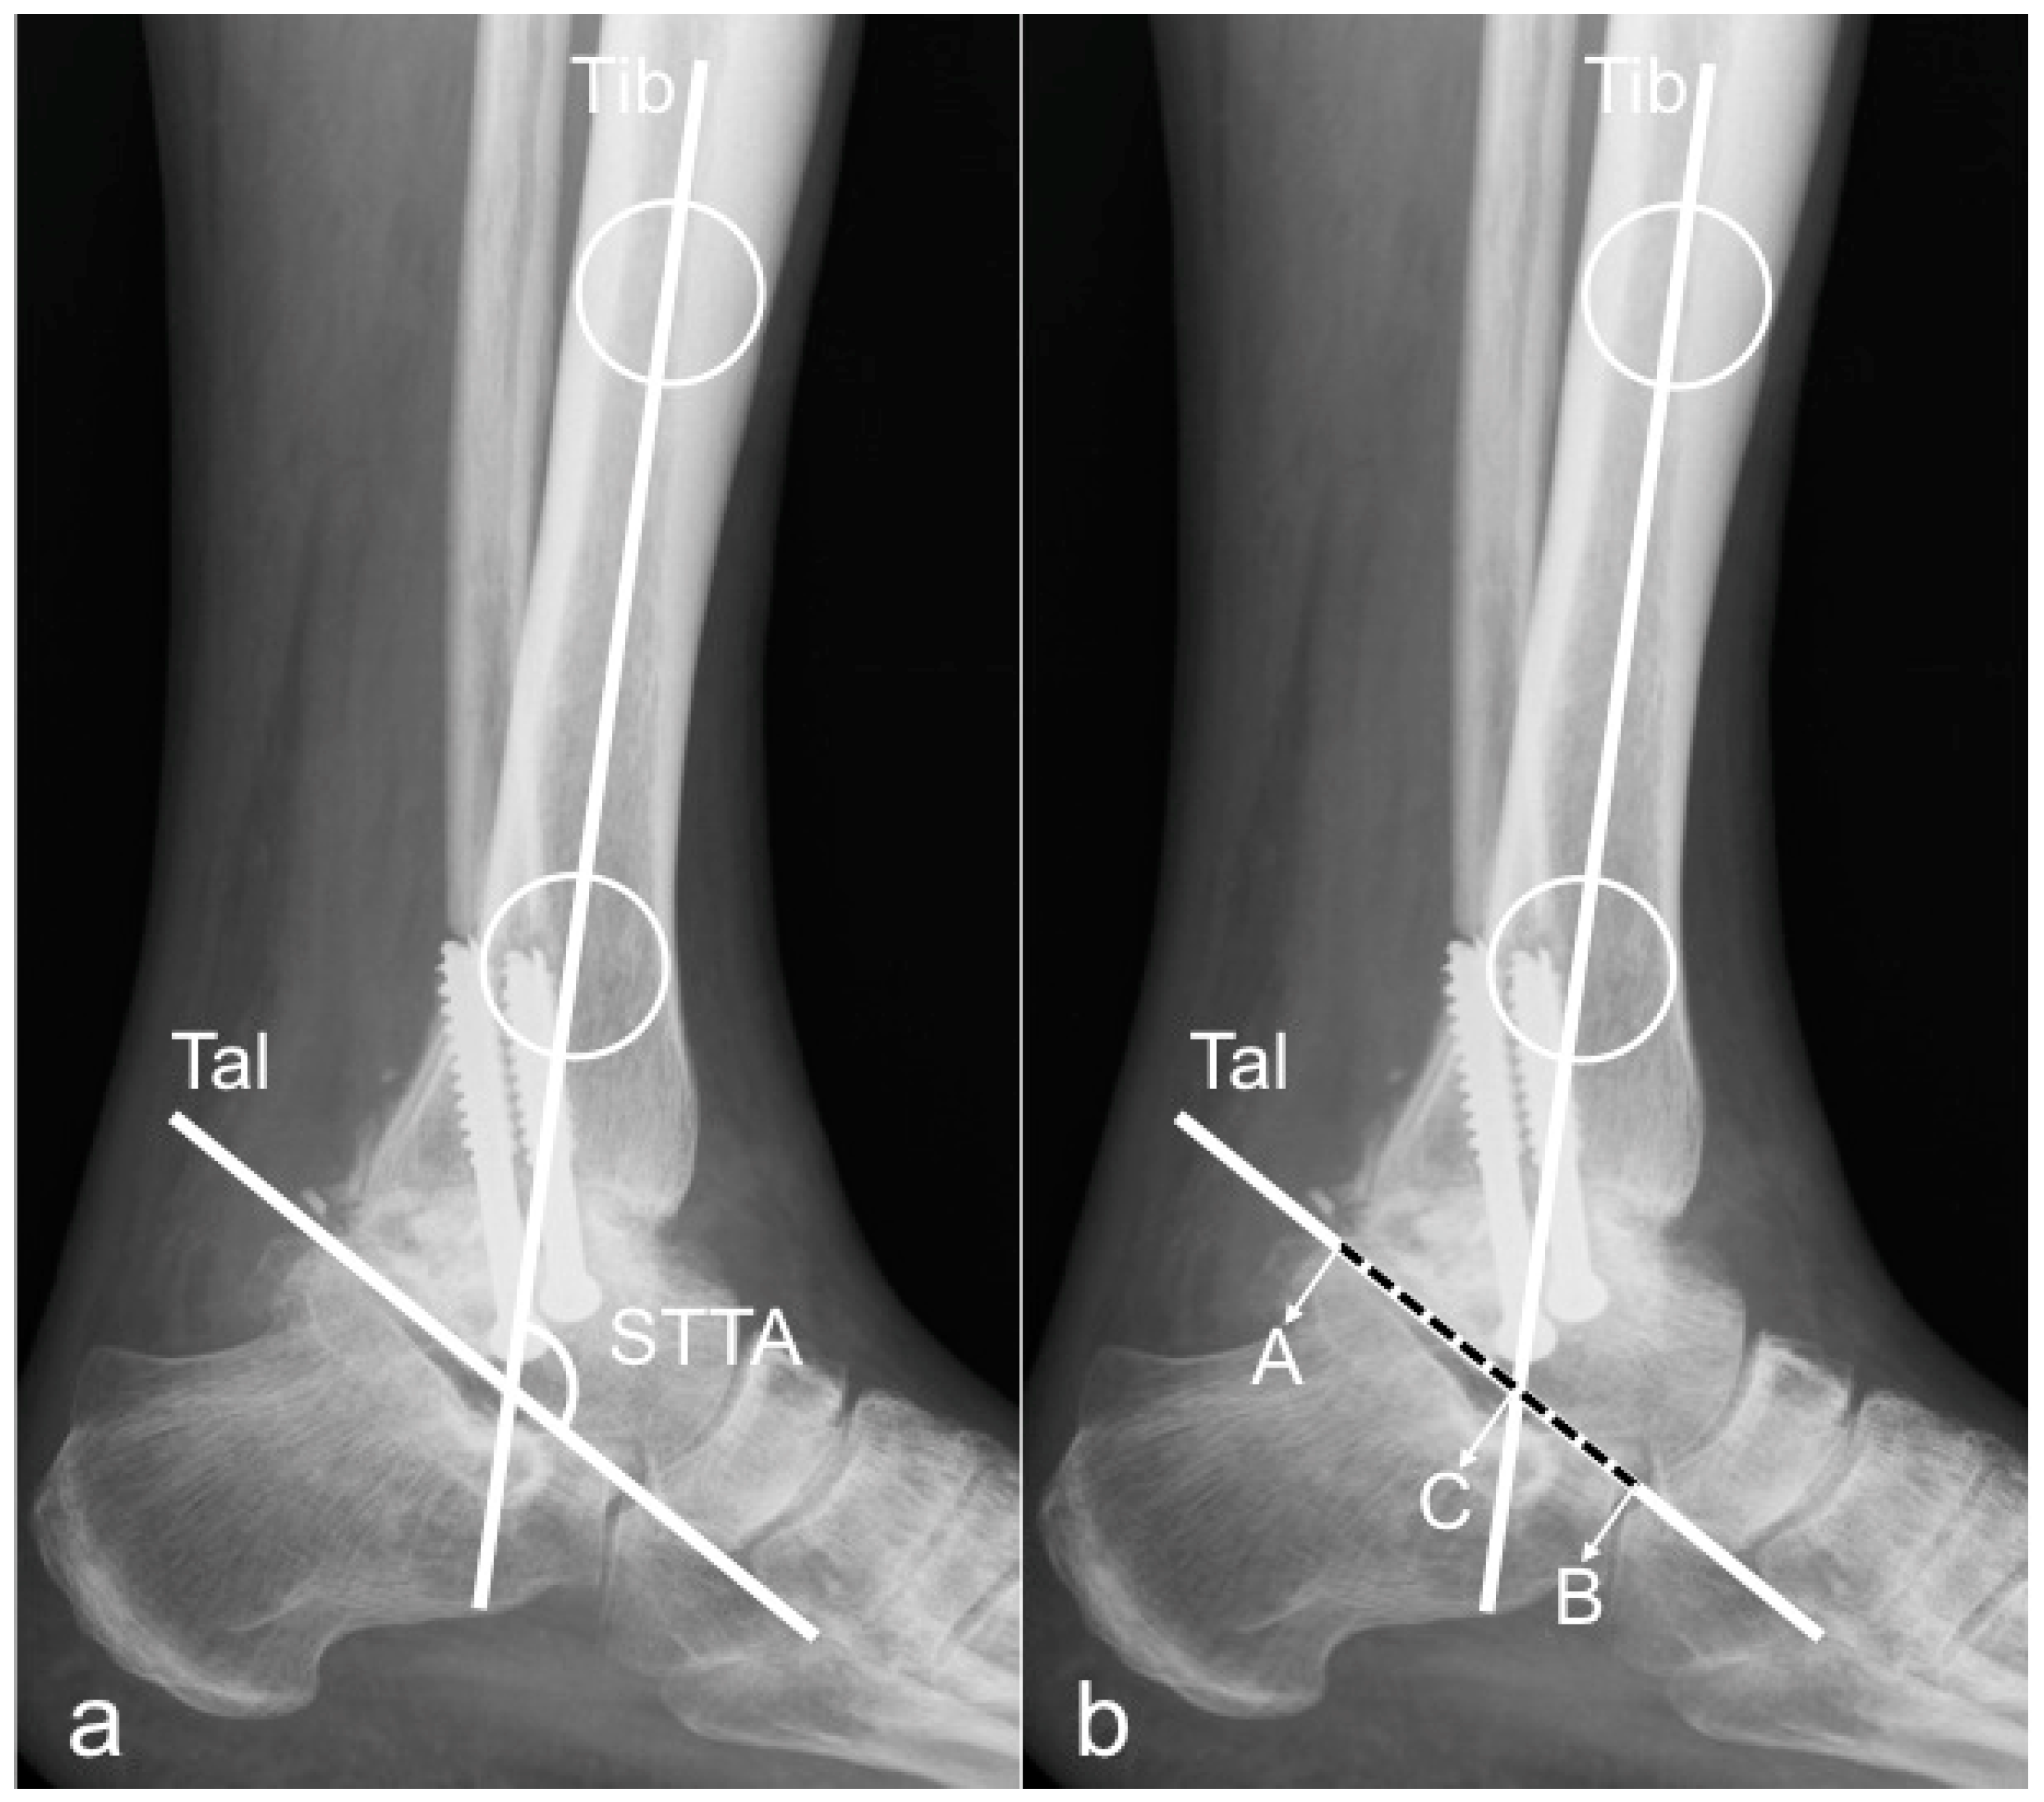

2.1. Radiographic Measurements

- tibCOR:

- procLAT:

- the distance from the tip of the lateral process of the talus to the longitudinal axis of the tibia [9].